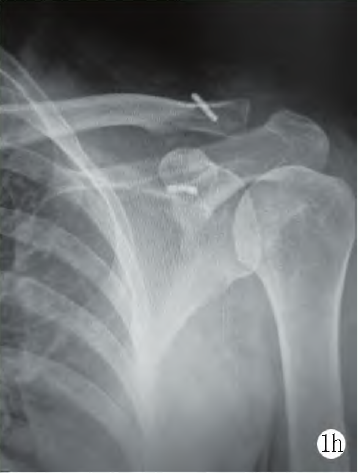

所有患者均獲隨訪9~15 個月, 平均(12.7±3.3)個月。VAS 評分由術前的(5.6±0.3)分顯著減少至末次隨訪時的(0.6±0.1)分(P<0.05)。肩關節(jié)Constant 評分由術前的(45.5±17.7)分顯著增加至末次隨訪的(88.8±14.6)分(P<0.05)。肩關節(jié)外展、外旋、內旋、前屈活動度分別由術前的(54.9±6.3)°、(31.9±2.3)°、(12.9±3.3)°、(65.9±12.3)°顯著增加至末次隨訪時(162.9±7.6)°、(85.68±7.57)°、(65.1±5.6)°、(116.7±23.3)°,差異均有統(tǒng)計學意義(P<0.05)。所有患者在末次隨訪時肩鎖關節(jié)處無異常隆起,外觀正常。末次隨訪時,所有患者肩關節(jié)正側位X 線片顯示肩鎖關節(jié)脫位已復位,解剖關系正常(圖1h)。

1h: 末次隨訪時正位X 線片顯示肩鎖關節(jié)解剖復位,鈦板位置好

本研究中采用的喙突側固定四葉草鈦板聯合鎖骨側的可調節(jié)帶袢鈦板聯合固定肩鎖關節(jié),很好地避免了復位張力過大這一問題。末次隨訪時,所有患者的VAS 評分明顯優(yōu)于術前;肩關節(jié)Constant 評分明顯高于術前;所有患者的肩關節(jié)活動度明顯高于術前,差異有統(tǒng)計學意義(P<0.05)。所有患者在末次隨訪時肩鎖關節(jié)處無異常隆起,外觀正常。末次隨訪時,所有患者拍攝肩關節(jié)正側位X線片顯示肩鎖關節(jié)脫位已復位,解剖關系正常。